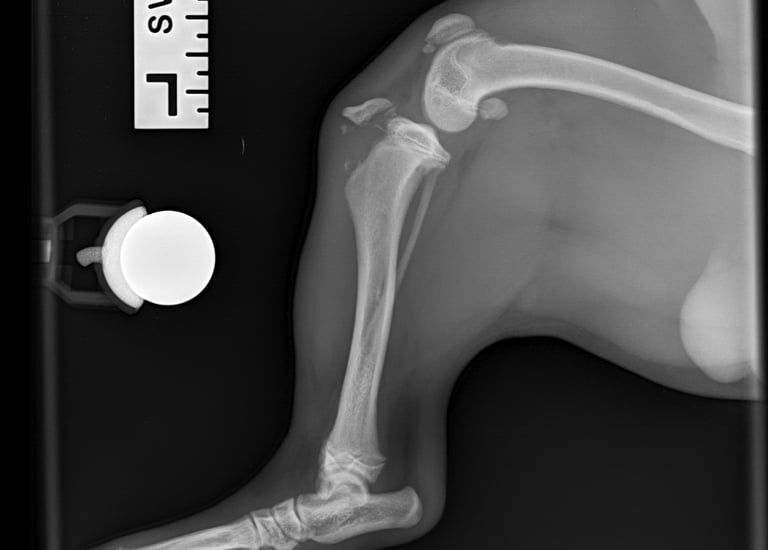

Six-week follow-up radiographs showed good ossification and healing of the fracture line, with progressive improvement also noted in the patellar avulsion lesion (Figs. 5 and 6).

Fig. 5

Fig. 6